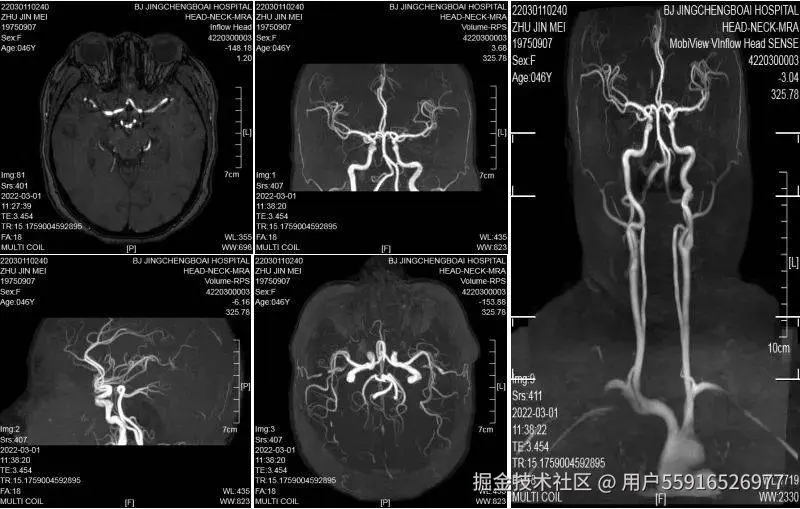

脑部核磁共振功能较多,“一站式”可分为不同的扫描序列和成像,包括头部核磁平扫(MRI)、脑血管成像(MRA)、弥散成像(DWI)、磁敏感成像(SWI)。MRI可查看颅内是否有脑肿瘤、脑梗塞、发育畸形等疾病;MRA可用来发现颅内动脉瘤、动静脉畸形等血管疾病;DWI常用来判断是否发生急性脑缺血;SWI对微小静脉出血诊断敏感。我院影像科可以通过一次扫描完成脑内占位、血管疾病、脑梗的检查,为临床提供较为全面的诊断依据。

非增强性脑血管成像(MRA)

MRA是一种无创、无辐射、简便经济、精准的脑血管筛查方法,相较脑血管CT三维重建(CTA)和脑血管造影(DSA)则需要注射造影剂,在X射线下辅助完成检查,二者只在进一步确诊脑血管疾病时考虑使用。